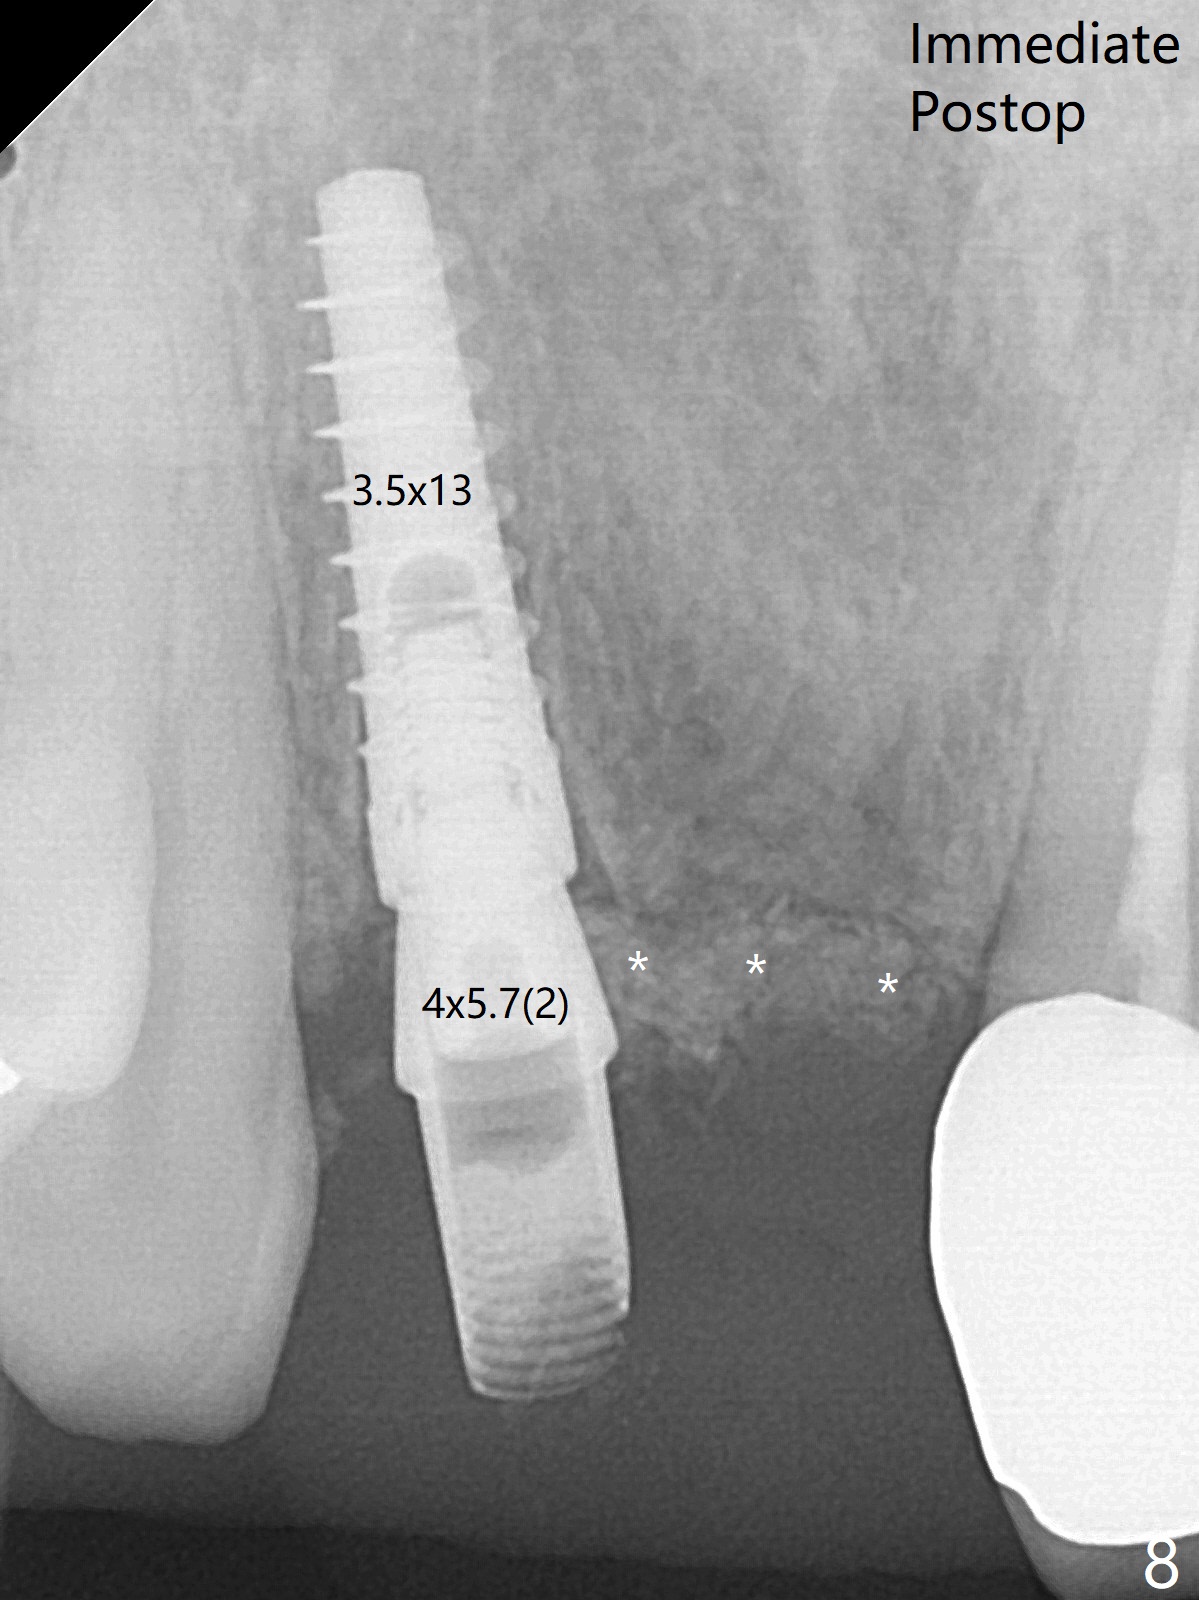

拆除部分桥发现:中,侧切牙牙龈红肿(图一),不利于切口和伤口愈合。不过还是在中切牙区切开,牙龈相当厚,有利于今后牙龈形成凹陷和乳头。坏消息是近远中距离太短,不利于植牙以及今后局部卫生维护,所以决定只在侧切牙种植(图二,三),完成钻洞后,颊侧根尖穿孔植骨,然后植入植体,即刻放置修复基台(图四 (*:牙龈乳头)),暴露基台牙龈缘,制作临时悬臂桥 (图五),两个中切牙牙冠长度差不多,插入临时桥时颊侧牙龈乳头基本形成(图六:*),缝合前颊侧,腭侧牙龈瓣下放置粘性骨块(图七,八:* )和PRF膜(图七:^)。最后使用牙周敷料。但愿术后牙龈炎症消失,形成良好牙龈乳头和pontic concavity。 其实由于口腔卫生习惯,术后十七天颊侧牙龈仍红肿(图九),而腭侧正常。如果口腔卫生改善而红肿依然存在,让实验室制作临时桥。术后一个月颊侧牙龈红肿好些(图十),好像骨粉丢失少许,可能与水枪使用有关。右上1牙冠显得太短(*)。也太肥大,因为右上1切缘太颊侧,与左上1对比(图十一:*)。由于颊侧牙龈(图十二:B)术中推向颊侧,与腭侧(P)牙龈之间放置大量粘性骨粉,术后一个月骨粉(<)形成牙龈,形成凹陷。颊侧萎缩不再明显了。右上1牙冠颈部多加些树脂,牙齿就显得长的多(图十三:箭头)。与侧切牙之间颈部故意留下间隙(*),让牙龈入位(空箭头),形成龈乳头。当右上1临时牙冠切缘(图十四:*)移到腭侧,外形改观不少。下次改善侧切牙唇侧。术后两个月三个星期牙龈红肿好像减轻,牙龈没有进入切牙间隙,干脆用树脂关闭(图十五:> <)。下次减少侧切牙切缘(^),适当增加中切牙长度(上提牙龈)。术后3.5个月植体好像整合,基台完全就位(图十六)。术后3.5个月Pontic凹陷形成,但是1,2之间龈乳头始终无法形成(图十七)。以后类似病例应该多种植一个。此例草率取模,可能需要临时粘固,观察植体近中颊侧所谓瘘道,必要刮治。由于比色不佳,需要实验室颜色更改,病人强化卫生,术后七个月,永久性牙冠粘固前,局部牙龈健康(图十八)。